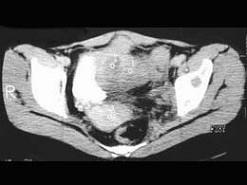

问题 患者,女,54岁,因反复左髋、左下肢疼伴左下肢活动障碍约半年,请结合所提供的图像,选择最佳选项 ( )

选项 A、Ewing肉瘤 B、骨巨细胞瘤 C、滑膜肉瘤 D、骨转移瘤 E、骨髓瘤

答案 A